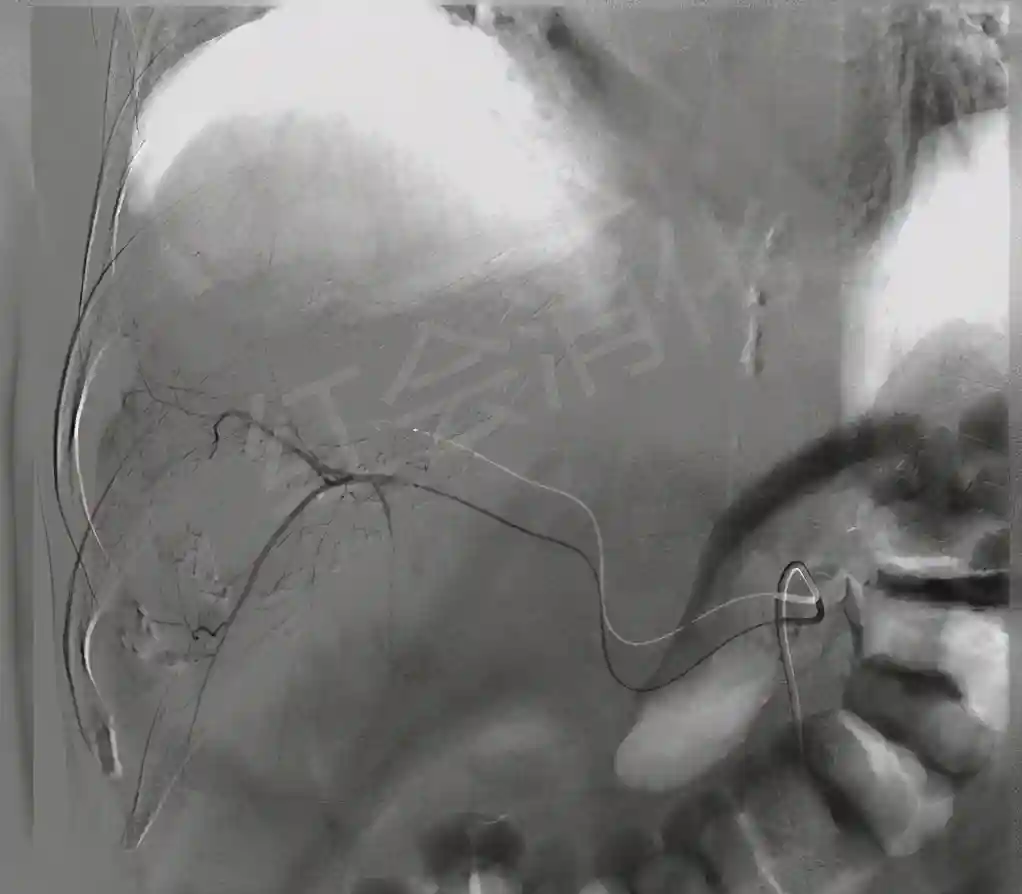

栓塞前造影

超选后造影

栓塞后造影